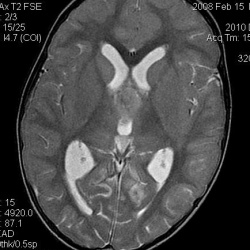

Пациент, 30 лет. Пришел на МРТ шейного отдела позвоночника с жалобами на боли в затылочной области. Во время исследования обратили внимание на образование в мозжечке, после чего была выполнена МРТ...